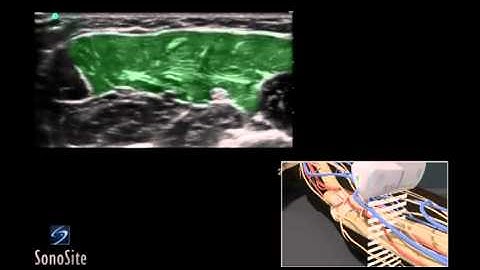

Nerve blocks explained (3D Animation)